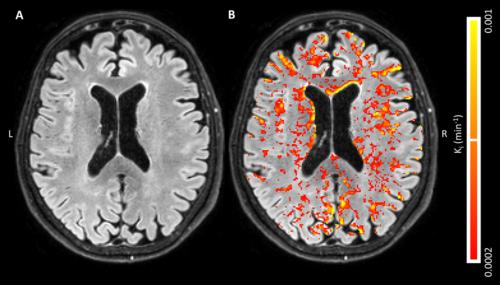

Global, diffusely distributed blood-brain barrier (BBB) leakage in patients with early Alzheimer’s disease (AD) suggests that a compromised BBB is part of the early pathology of AD and might be part of a cascade of pathologic events that eventually lead to cognitive decline, according to new Radiology research.

Harm J. van de Haar, MSc, of Maastricht University Medical Center in Maastricht, the Netherlands, and colleagues found that the BBB leakage rate was significantly higher in patients compared with that in control subjects in the total gray matter and cortex. For this pilot study, 16 patients with early AD and 17 healthy age-matched control subjects underwent dynamic contrast material–enhanced MRI sequence with dual time resolution for 25 minutes.

Patients had a significantly higher volume fraction of the leaking brain tissue in the GM, normal-appearing white matter, deep gray matter and cortex. When all subjects were considered, scores on the Mini-Mental State Examination decreased significantly with increasing leakage in the deep gray matter and cortex.

“We found an increased BBB leakage rate in the gray matter of patients with early AD. By also showing very subtle BBB impairment in the white matter, leakage volume proved to be even more sensitive to the differences in BBB leakage than was the leakage rate,” the authors write.